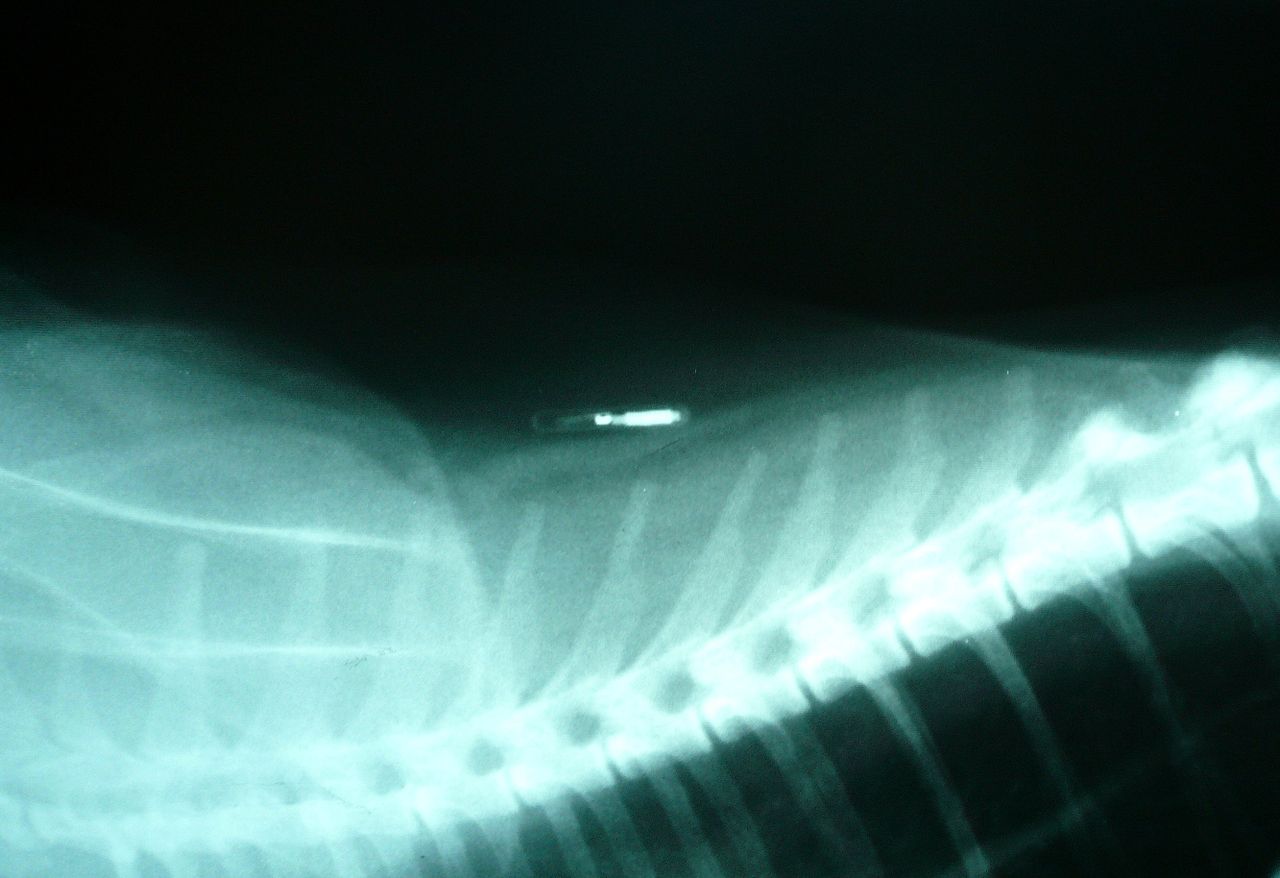

Стерилизация – это операция по удалению репродуктивных органов у животных женского пола и удалению семенников у животных мужского пола. В обоих случаях операция проводится под наркозом. Полостные операции подразумевают снятие швов по прошествии нескольких дней.